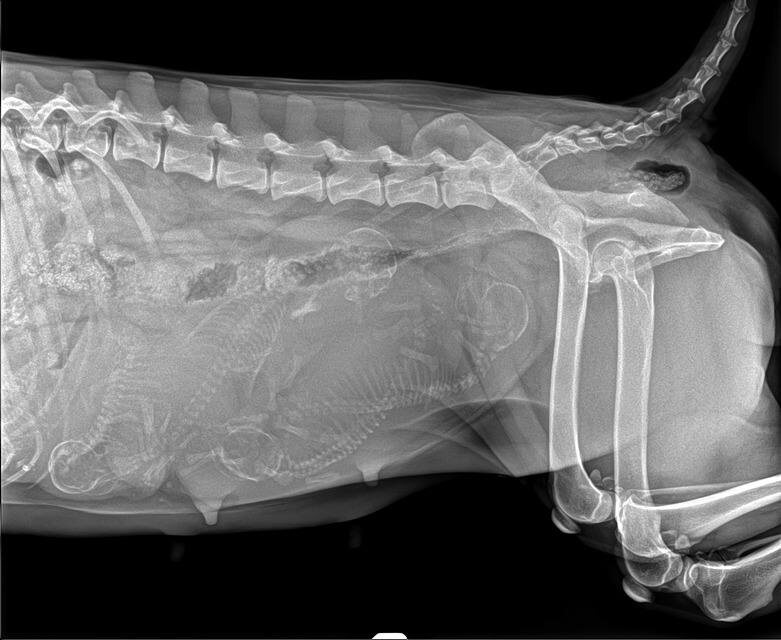

На всякий случай сделали рентген, исключить наличие инородных предметов.

И заодно посчитали щеночков❤️❤️❤️

Готовлю местечко для малышей и мамочки и разглядываю снимки😀 Я насчитала 5 щеночков, а вы?)))))